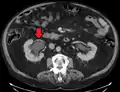

CT scan of bilateral hydronephrosis due to a bladder cancer